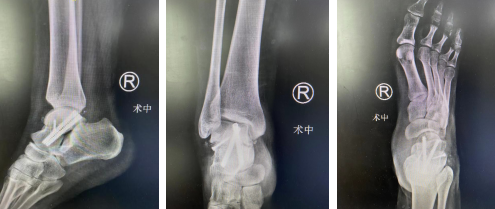

在踝关节镜下探查,将骨折脱位复位,骨科机器人三维扫描,电脑软件模拟规划置钉,精准固定骨折。

术后X线,距骨骨折复位,螺钉精确固定